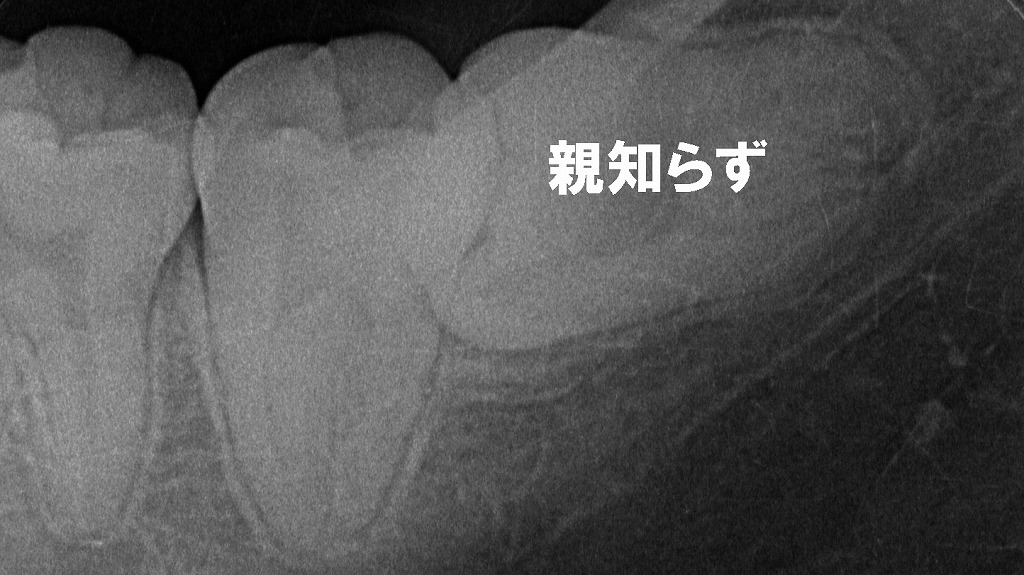

🪥 歯周病の治療

スケーリング(歯石除去)やルートプレーニングで、歯ぐきの中の汚れを除去します。

歯周病治療による歯ぐきの改善|術前・術後の比較

歯周病治療による変化を示した術前・術後の比較写真です。術前は歯ぐきの腫れや赤み、歯肉退縮がみられ、炎症が慢性化していましたが、歯石除去を中心とした歯周病治療後は炎症が改善し、歯ぐきが引き締まった健康的な状態へと回復しています。適切な治療と日々のプラークコントロールが、歯を長く守るために重要であることが分かります。

🧑⚕️ 親知らずの抜歯・矯正相談

親知らずの圧迫や歯の移動による違和感には、早めの歯科相談が安心です。